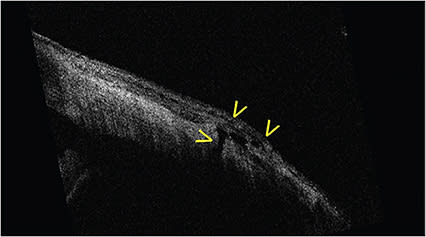

Anterior segment iOCT may also be useful for the retinal surgeon. Here, iOCT of the pars plana immediately after trocar cannulas are removed clearly illustrates the rationale for beveled vitrectomy trocar cannula placement. In this image of the pars plana after the cannulas are removed, an open 25-gauge sclerotomy is present with a small conjunctival bleb (Figure 7). This is in sharp contradistinction to this much more beveled sclerotomy which is closed and does not have an overlying conjunctival bleb (Figure 8, page 52).

Figure 7. The pars plana after the cannulas are removed; an open 25-gauge sclerotomy is present with a small conjunctival bleb.

Figure 8. With a more beveled sclerotomy, which is closed, there is no overlying conjunctival bleb.